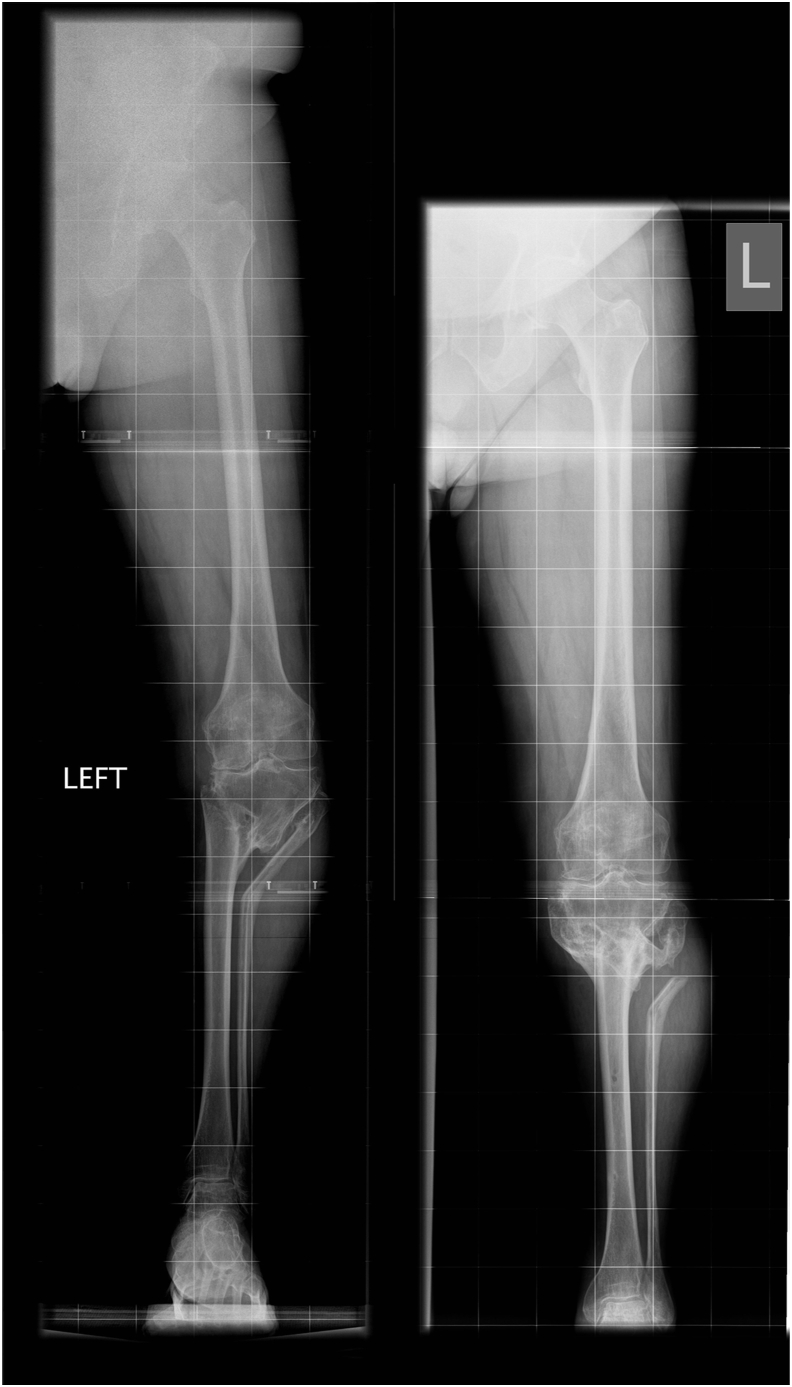

5.3. Staged deformity correction & TKA

Two-stage procedures allow for recovery between osteotomy and arthroplasty. In some cases, osteotomy and correction of malalignment delays the need for TKA due to alleviation of symptoms (Fig. 7a and b). In selected young patients with deformity, osteotomy can be converted to HTO, thereby offloading the medial compartment and deferring the TKA, thus benefitting from the decreased life-time risk of revision with increasing age.33

Fig. 7.

Planned for 2 stage TKA - Deformity correction alleviated symptoms and consequently need for TKA7a – pre op Translation deformity, significant medial MAD and medial compartment grade 4 OA7b – Post correction, neutral alignment. At 13 years FU patient with minimal symptoms and does not require TKA.

Various techniques are available for fixation of deformity correction osteotomies.8,34 Internal fixation, although less cumbersome for the patient than external fixation, relies on the accuracy of deformity correction achieved, with no option of fine tuning the deformity correction post-operatively, and often does not address the dynamic component of the deformity. It is usually used for correction of femoral deformities due to convenience. In the recent past, external fixator assisted internal fixation has been utilized to improve accuracy (Fig. 8a–d). Antegrade nails, possibly inserted with navigation or patient-specific instrumentation (PSI) have an advantage over retrograde femoral nails as they can potentially be left in-situ.

Fig. 8.

2 stage surgery - Stage 1 Osteotomy, Stage 2 TKA8a – pre op multi apical deformity8b – Fixator assisted 2 level osteotomy and internal fixation to correct the deformity. Osteotomies healed8c & d – Post TKR with long stem tibia to support the osteotomy site.

Gradual correction with circular frame is preferred when soft tissue quality is poor, in complex deformities, when patients have had multiple procedures in the past or to minimise the risk to peroneal nerve when correcting severe valgus deformity.35 Circular external fixation, although relatively more cumbersome, provides the most accurate deformity correction whilst addressing both static and dynamic components of the deformity simultaneously.